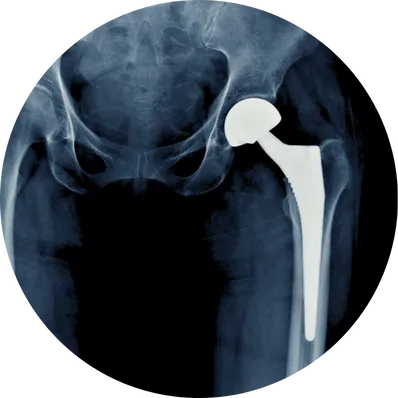

Types of Joint Replacement

Joint Replacement Treatment (Surgical Approach)